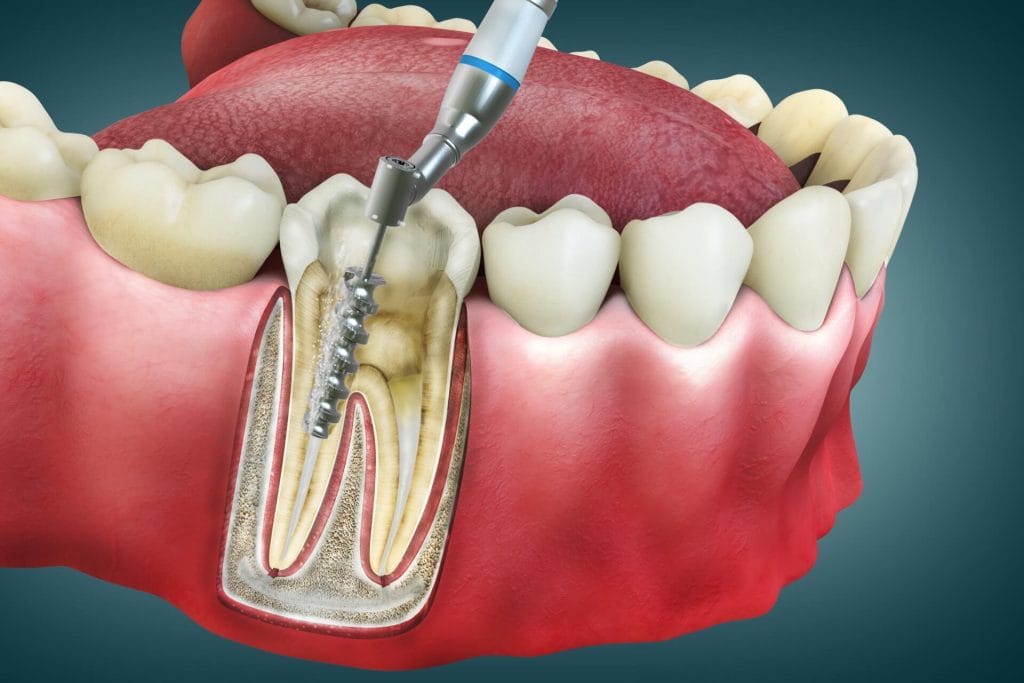

- Root Canal Treatment (RCT) or Endodontic Treatment, is a dental procedure done when tooth decay reaches the pulp (innermost layer of the tooth), causing inflammation. It is necessary to save the damaged tooth to prevent extraction. An endodontist (Root Canal specialist) performs this procedure. The procedure involves.

Removal of inflamed or infected Tooth Material. - Cleaning and disinfection.

- Fill and seal with an inert material.

- Restoration and crown/cap.